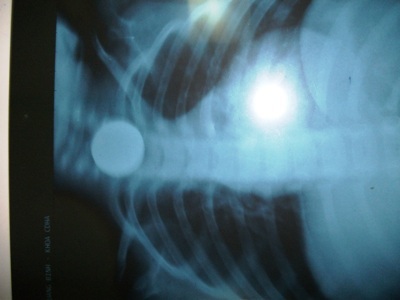

Trước đó, cháu Tường Vi được đưa vào cấp cứu tại Bệnh viện Hữu Nghị Việt Nam – Cuba Đồng Hới trong tình trạng khó thở, nuốt nghẹn, đau tức vùng cổ. Qua chụp phim X.quang, các bác sỹ bệnh viện này phát hiện một đồng xu đang nằm mắc kẹt ở cổ và đã tiến hành chuyển phòng mổ nội soi, gắp ra đồng tiền xu với kích thước khoảng 2cm.

Tấm phim X.Quang thấy rõ hình tiền đồng xu ở trong bụng cháu Tường Vi